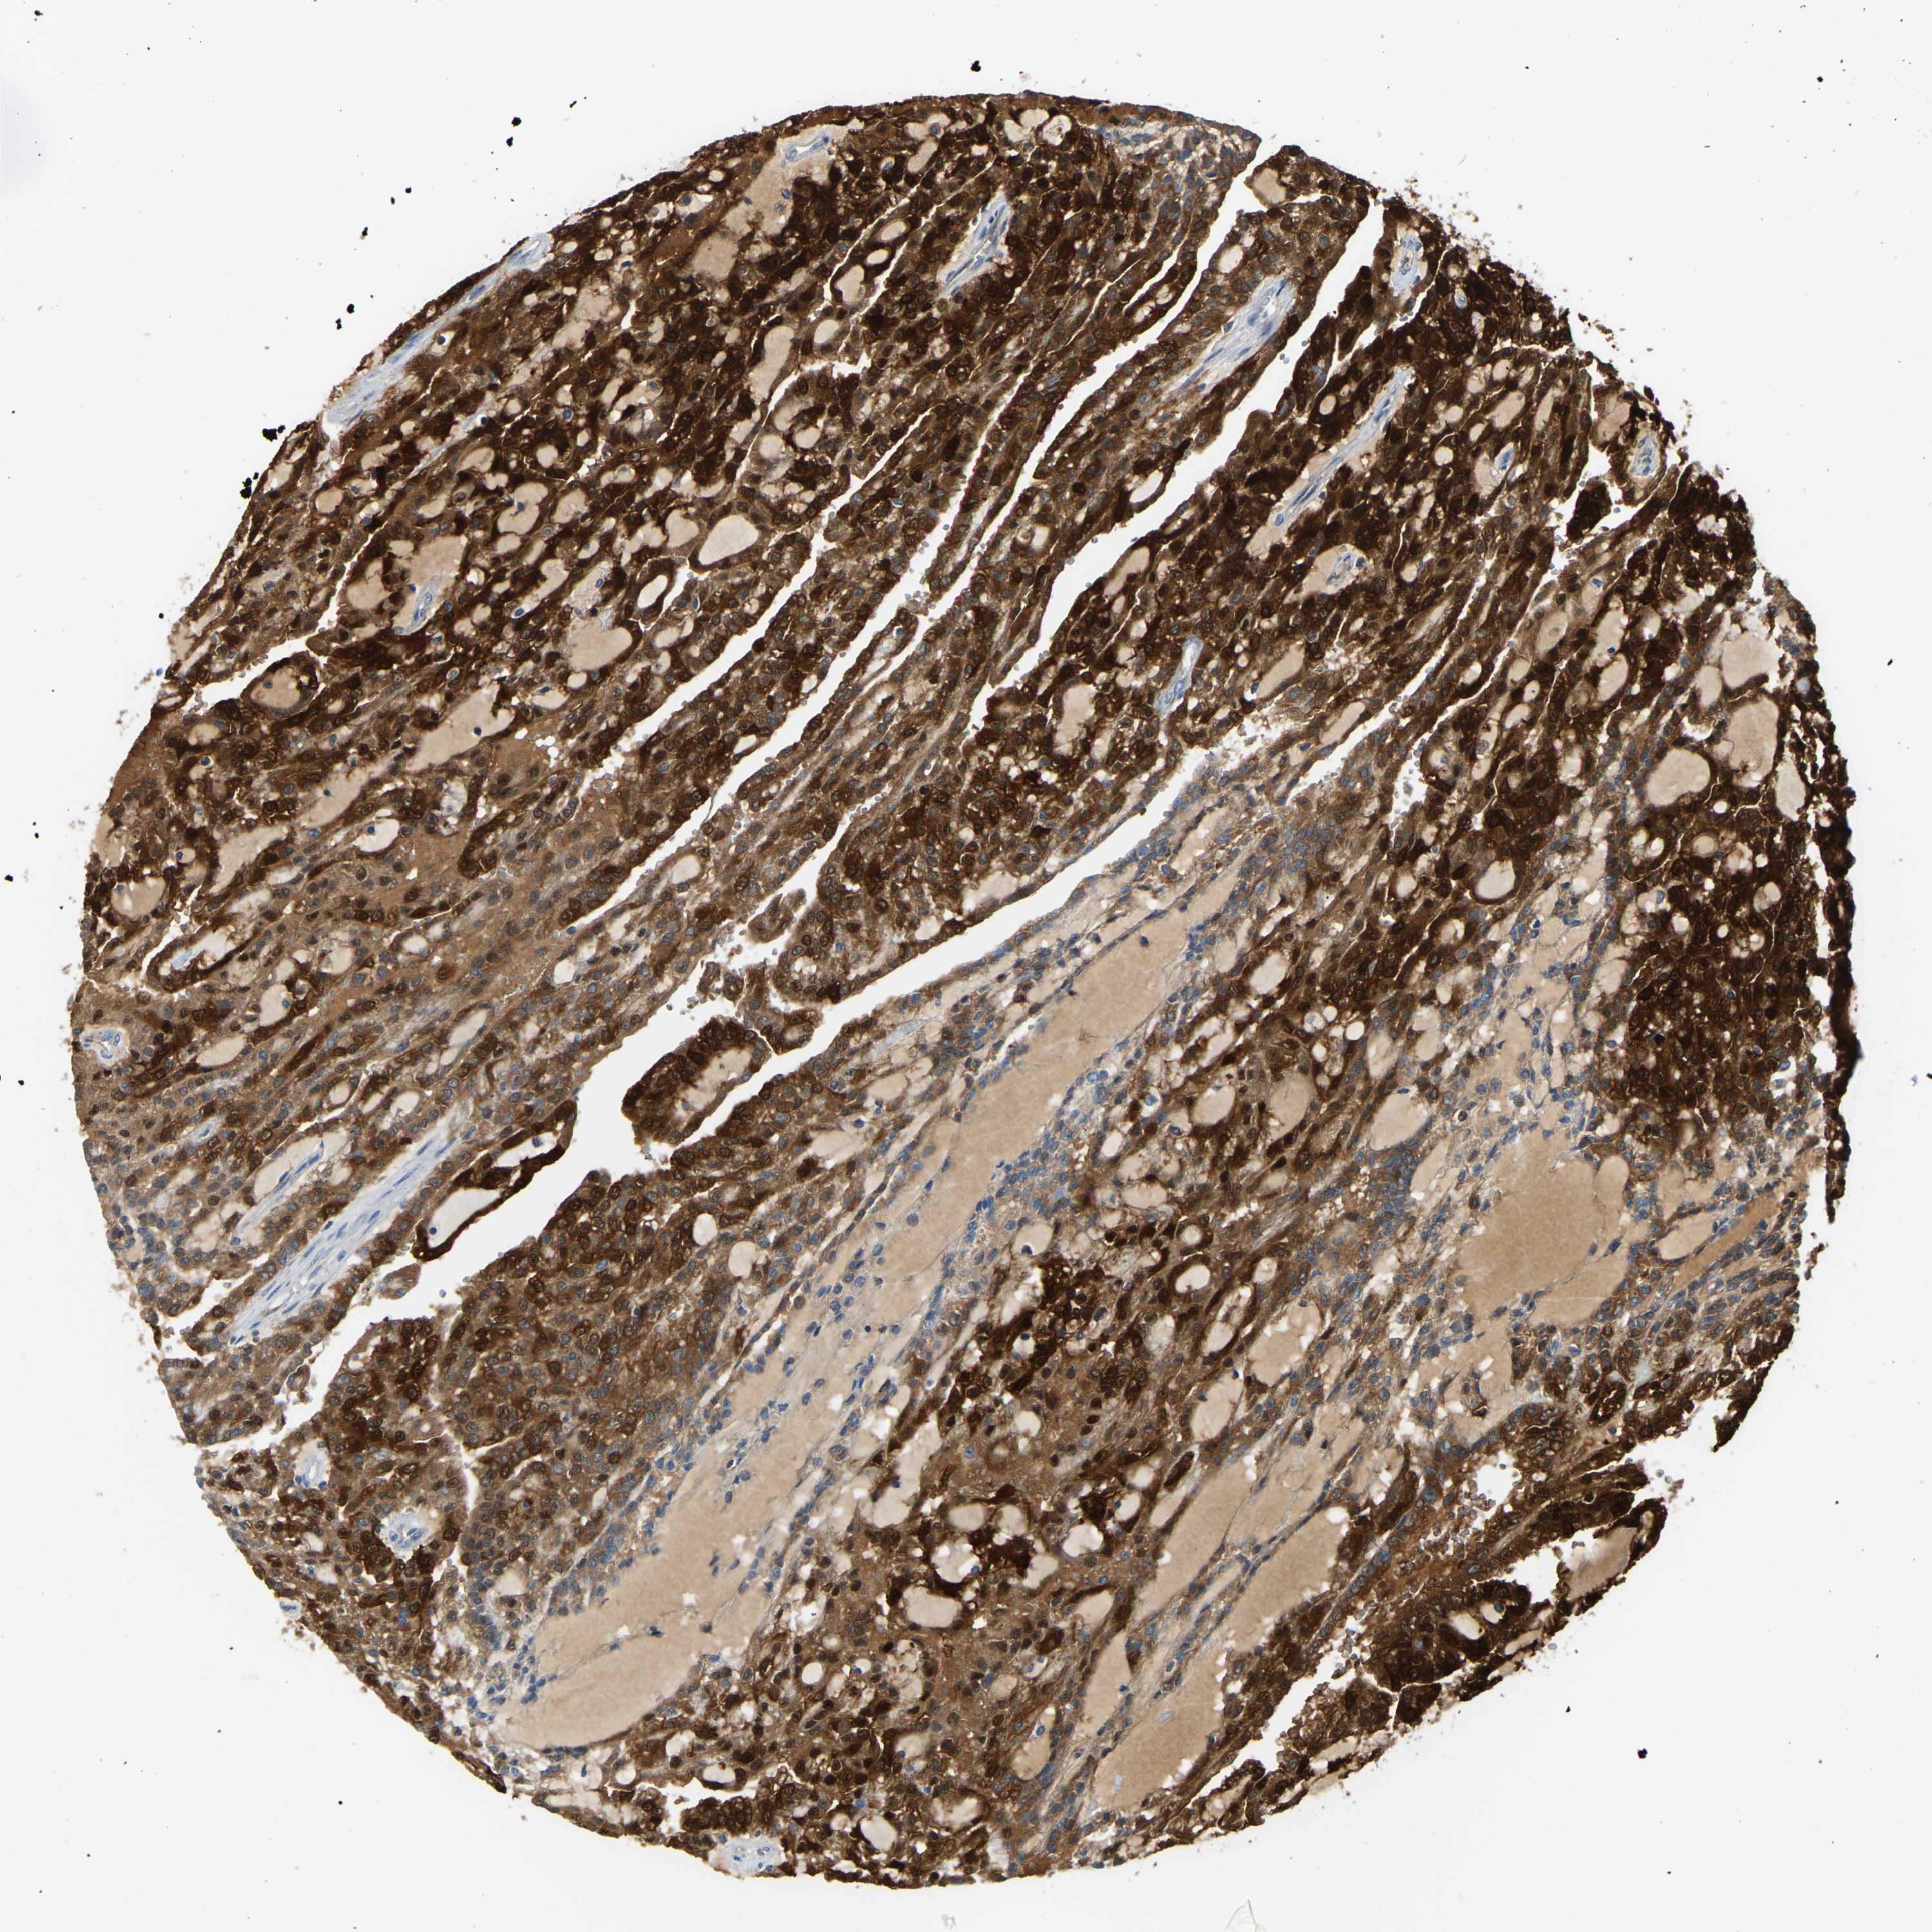

KIDNEY RENAL CLEAR CELL CARCINOMA (TCGA) - Interactive survival scatter ploti

The Survival Scatter plot shows the clinical status (i.e. dead or alive) for all individuals in the patient cohort, based on the same data that underlies the corresponding Kaplan-Meier plots. Patients that are alive at last time for follow-up are shown in blue and patients who have died during the study are shown in red.

The x-axis shows the expression levels (FPKM) of the investigated gene in the tumor tissue at the time of diagnosis. The y-axis shows the follow-up time after diagnosis (years). Both axes are complimented with kernel density curves demonstrating the data density over the axes. The top density plot shows the expression levels (FPKM) distribution among dead (red) and alive patients (blue). The right density plot shows the data density of the survived years of dead patients with high and low expression levels respectively, stratified using the cutoff indicated by the vertical dashed line through the Survival Scatter plot. This cutoff is automatically defined based on the FPKM cutoff that minimizes the p-score. The cutoff can be changed by dragging the vertical line or by entering a cutoff value in the square labeled "Current cut-off".

Under the Survival Scatter plot the p-score landscape (black curve; left axis) is shown together with dead median separation (red curve; right axis). Dead median separation is the difference in median mRNA expression between patients who have died with high and low expression, respectively. It is calculated as follows: median FPKM expression of dead patients with high expression - median FPKM expression of dead patients with low expression. This is intended to aid the user in visually exploring custom cutoffs and the associated p-scores and dead median separation.

Individual patient data is displayed and can be filtered by clicking on one or more of the category buttons on the top of the page. Categories describing expression level and patient information include: high, low, alive, dead, female, male and tumor stages. The scale of the x-axis can be toggled between linear and log-scale by clicking on the "x log" button. Mouse-over function shows TCGA ID, patient information and mRNA expression (FPKM) for each patient.

& Survival analysisi

Kaplan-Meier plots summarize results from analysis of correlation between mRNA expression level and patient survival. Patients were divided based on level of expression into one of the two groups "low" (under cut off) or "high" (over cut off). X-axis shows time for survival (years) and y-axis shows the probability of survival, where 1.0 corresponds to 100 percent.

GDA is potential prognostic, high expression is favorable in Kidney Renal Clear Cell Carcinoma (TCGA)

Best expression cut offi

: 8.38

Average pTPM 18.6

Number of samples 521